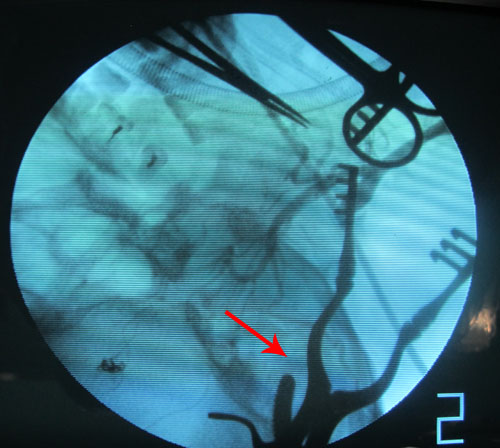

头颅MRA:左侧颈内动脉闭塞,前交通动脉供血,大脑中动脉显影浅淡。

颈动脉CE-MRA:左侧颈内动脉及左侧大脑中动脉闭塞;右侧椎动脉不完全闭塞。

2011年7月3日和7月4日,协作组张勤奕教授分别为这两位患者实施了左侧颈内动脉残根切除术。